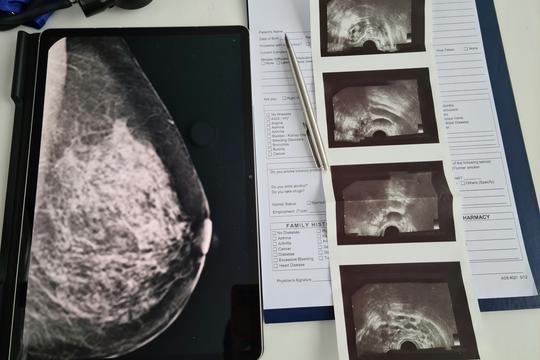

Foto: Unsplash+